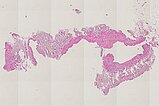

Histopathologischer Schnitt des gewonnenen Biopsiepräparates; Hämatoxylin-Eosin-Färbung, Übersichtsvergrößerung, 20-fach; gut sichtbar die unregelmäßige Wandstruktur der dysplastischen Gefäßräume, typisch für eine Gefäßmalformation. Wieder ist der eigentliche dysplastische Gefäßraum größer als das gewonnene Gewebestück. Daher ist die Gefäßwand auch nicht tubular dargestellt, sondern das Gefäß wie „umgestülpt“ und die Wand außen randbildend ohne ein eigentlich sichtbares rohrförmiges Gefäß. Das mit dargestellte Fettgewebe ist unspezifisch.

Hämatoxylin-Eosin-Färbung, 40-fache Vergrößerung als Übersicht; hier ein anderer Gefäßabschnitt dargestellt. Die unregelmäßige, zum Teil ganz fehlende Wandstruktur der dysplastischen Gefäßräume in der ganzen Läsion ist wiederum typisch für eine Gefäßmalformation.

Die histopathologische Aufarbeitung zeigte dann auch den typischen Befund einer benignen Gefäßläsion (CD31-positiv) mit dysplastischem, asymmetrisch unregelmäßigem Wandaufbau. Wie für solche Slow-flow-Gefäßmalformationen typisch, ist die glattmuskuläre Gefäßwand nicht überall gleich dick und symmetrisch ausgebildet, sondern fehlt zum Teil sogar ganz (SMA, EvG). Kaum Proliferation des beteiligten Gewebes (Ki67 sehr niedrig). Die fehlende WT1-Positivität der betroffenen Gefäßendothelien ist ein weiterer Hinweis auf eine Gefäßmalformation. Wesentlichstes histopathologisches Unterscheidungsmerkmal zwischen einer lymphatischen Malformation und einer venösen Malformation ist die immunhistochemische Anfärbung des Podoplanin der Gefäßendothelien der Läsion mittels des Antikörpers D2-40. Nur die Gefäßendothelzellen einer lymphatischen Malformation (D2-40 positiv) färben hier an. In dem Präparat zeigten sich zusätzlich auch multiple dysplastische Gefäßmalformationsareale, deren Gefäßendothel nicht mit D2-40 anfärbte, also handelte es sich hierbei um Anteile einer venösen Malformation. Die korrekte histopathologische Diagnose ist daher auch eine kombinierte venolymphatische Malformation. Die klinisch und in der Bildgebung klar im Vordergrund stehende lymphatische Komponente steht in dem Präparat der hier gewonnenen Stanzbiopsie aus der Läsion gegenüber der venösen Komponente eher im Hintergrund.